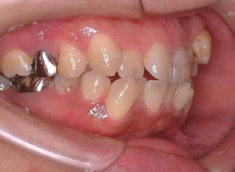

治療前

治療開始時